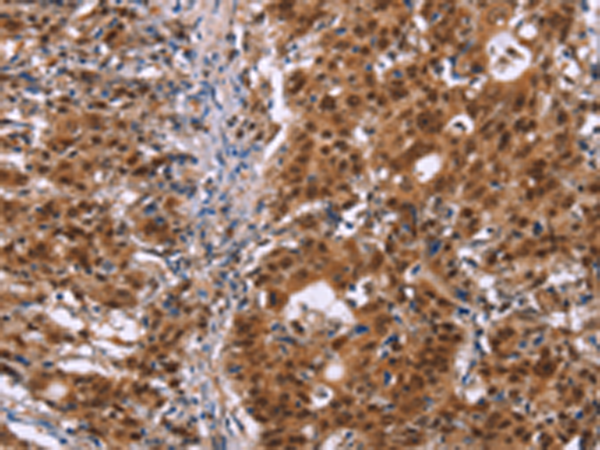

分类: 科研抗体货号: P03994别名: GLUT3应用: WB,IHC反应种属: Human